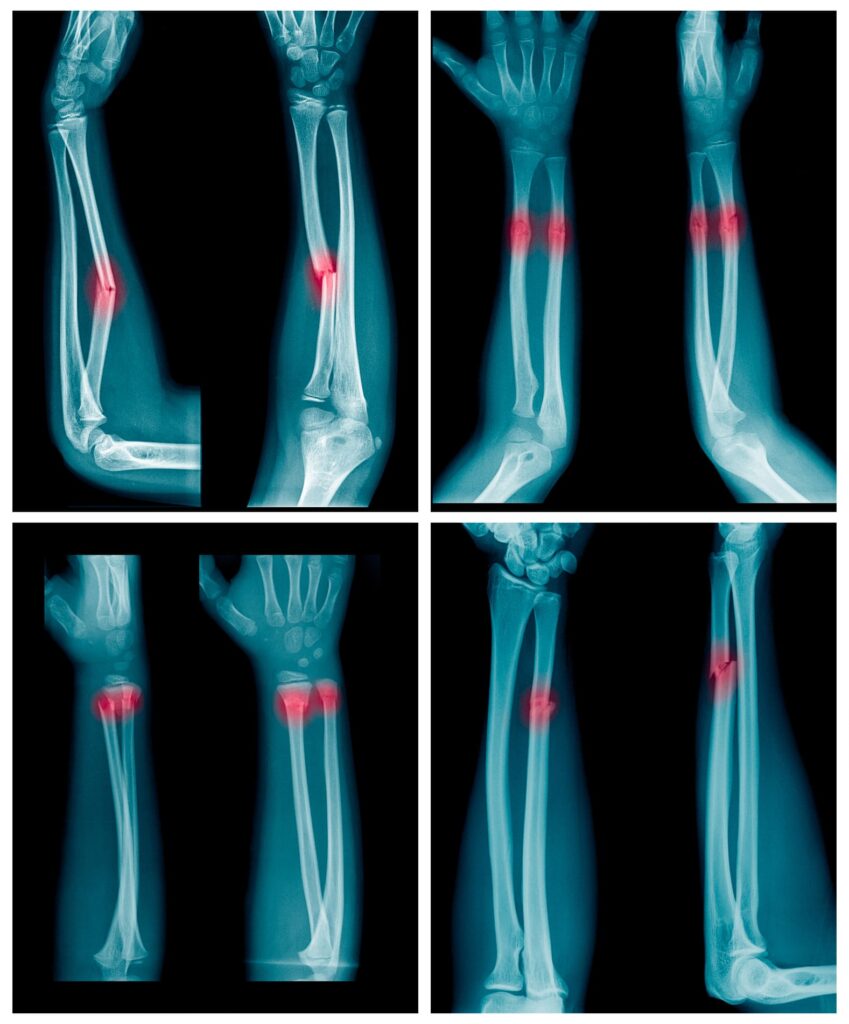

Knochenbruch der Speiche und der Hand- und Fingerknochen Symptome, Ursachen, Behandlung

Die Hand besteht aus 27 einzelnen Knochen (8 Handwurzelknochen, 5 Mittelhandknochen, 14 Fingerknochen). Jeder einzelne Knochen kann durch einen Unfall brechen und die Stücke können sich zueinander verschieben. Typische Vertreter eines Knochenbruches an der oberen Extremität, welchen wir anbieten können zu behandeln sind die Schlüsselbeinfraktur, distale Humerusfraktur, Ellenbogengelenksfraktur, Radiuskopffraktur, Unterarmfraktur, distale Radiusfraktur, Kahnbeinfraktur sowie Mittelhand- und Fingerfrakturen. An der unteren Extremität sind dies die Tibiakopffraktur, die Sprunggelenksfraktur, sowie Fuß- und Zehenfrakturen. Je nachdem welcher Knochen und in welcher Form er gebrochen ist, kann man den Bruch entweder mit einem Gips oder einer Operation behandeln. Das Ziel ist immer die beste Funktion wieder zu erreichen. Daher ist nicht nur eine schnelle ärztliche Behandlung, sondern auch die Nachbehandlung und die Durchführung von physiotherapeutischen Übungen entscheidend.

Die Behandlung von Unterarmfrakturen richtet sich nach dem Ort der Fraktur (Radius, Ulna oder beide), Frakturtyp (einfach, disloziert, offen, Trümmerfraktur), Alter des Patienten (Kinder vs. Erwachsene) und Begleitverletzungen (Nerven, Gefäße, Weichteile).